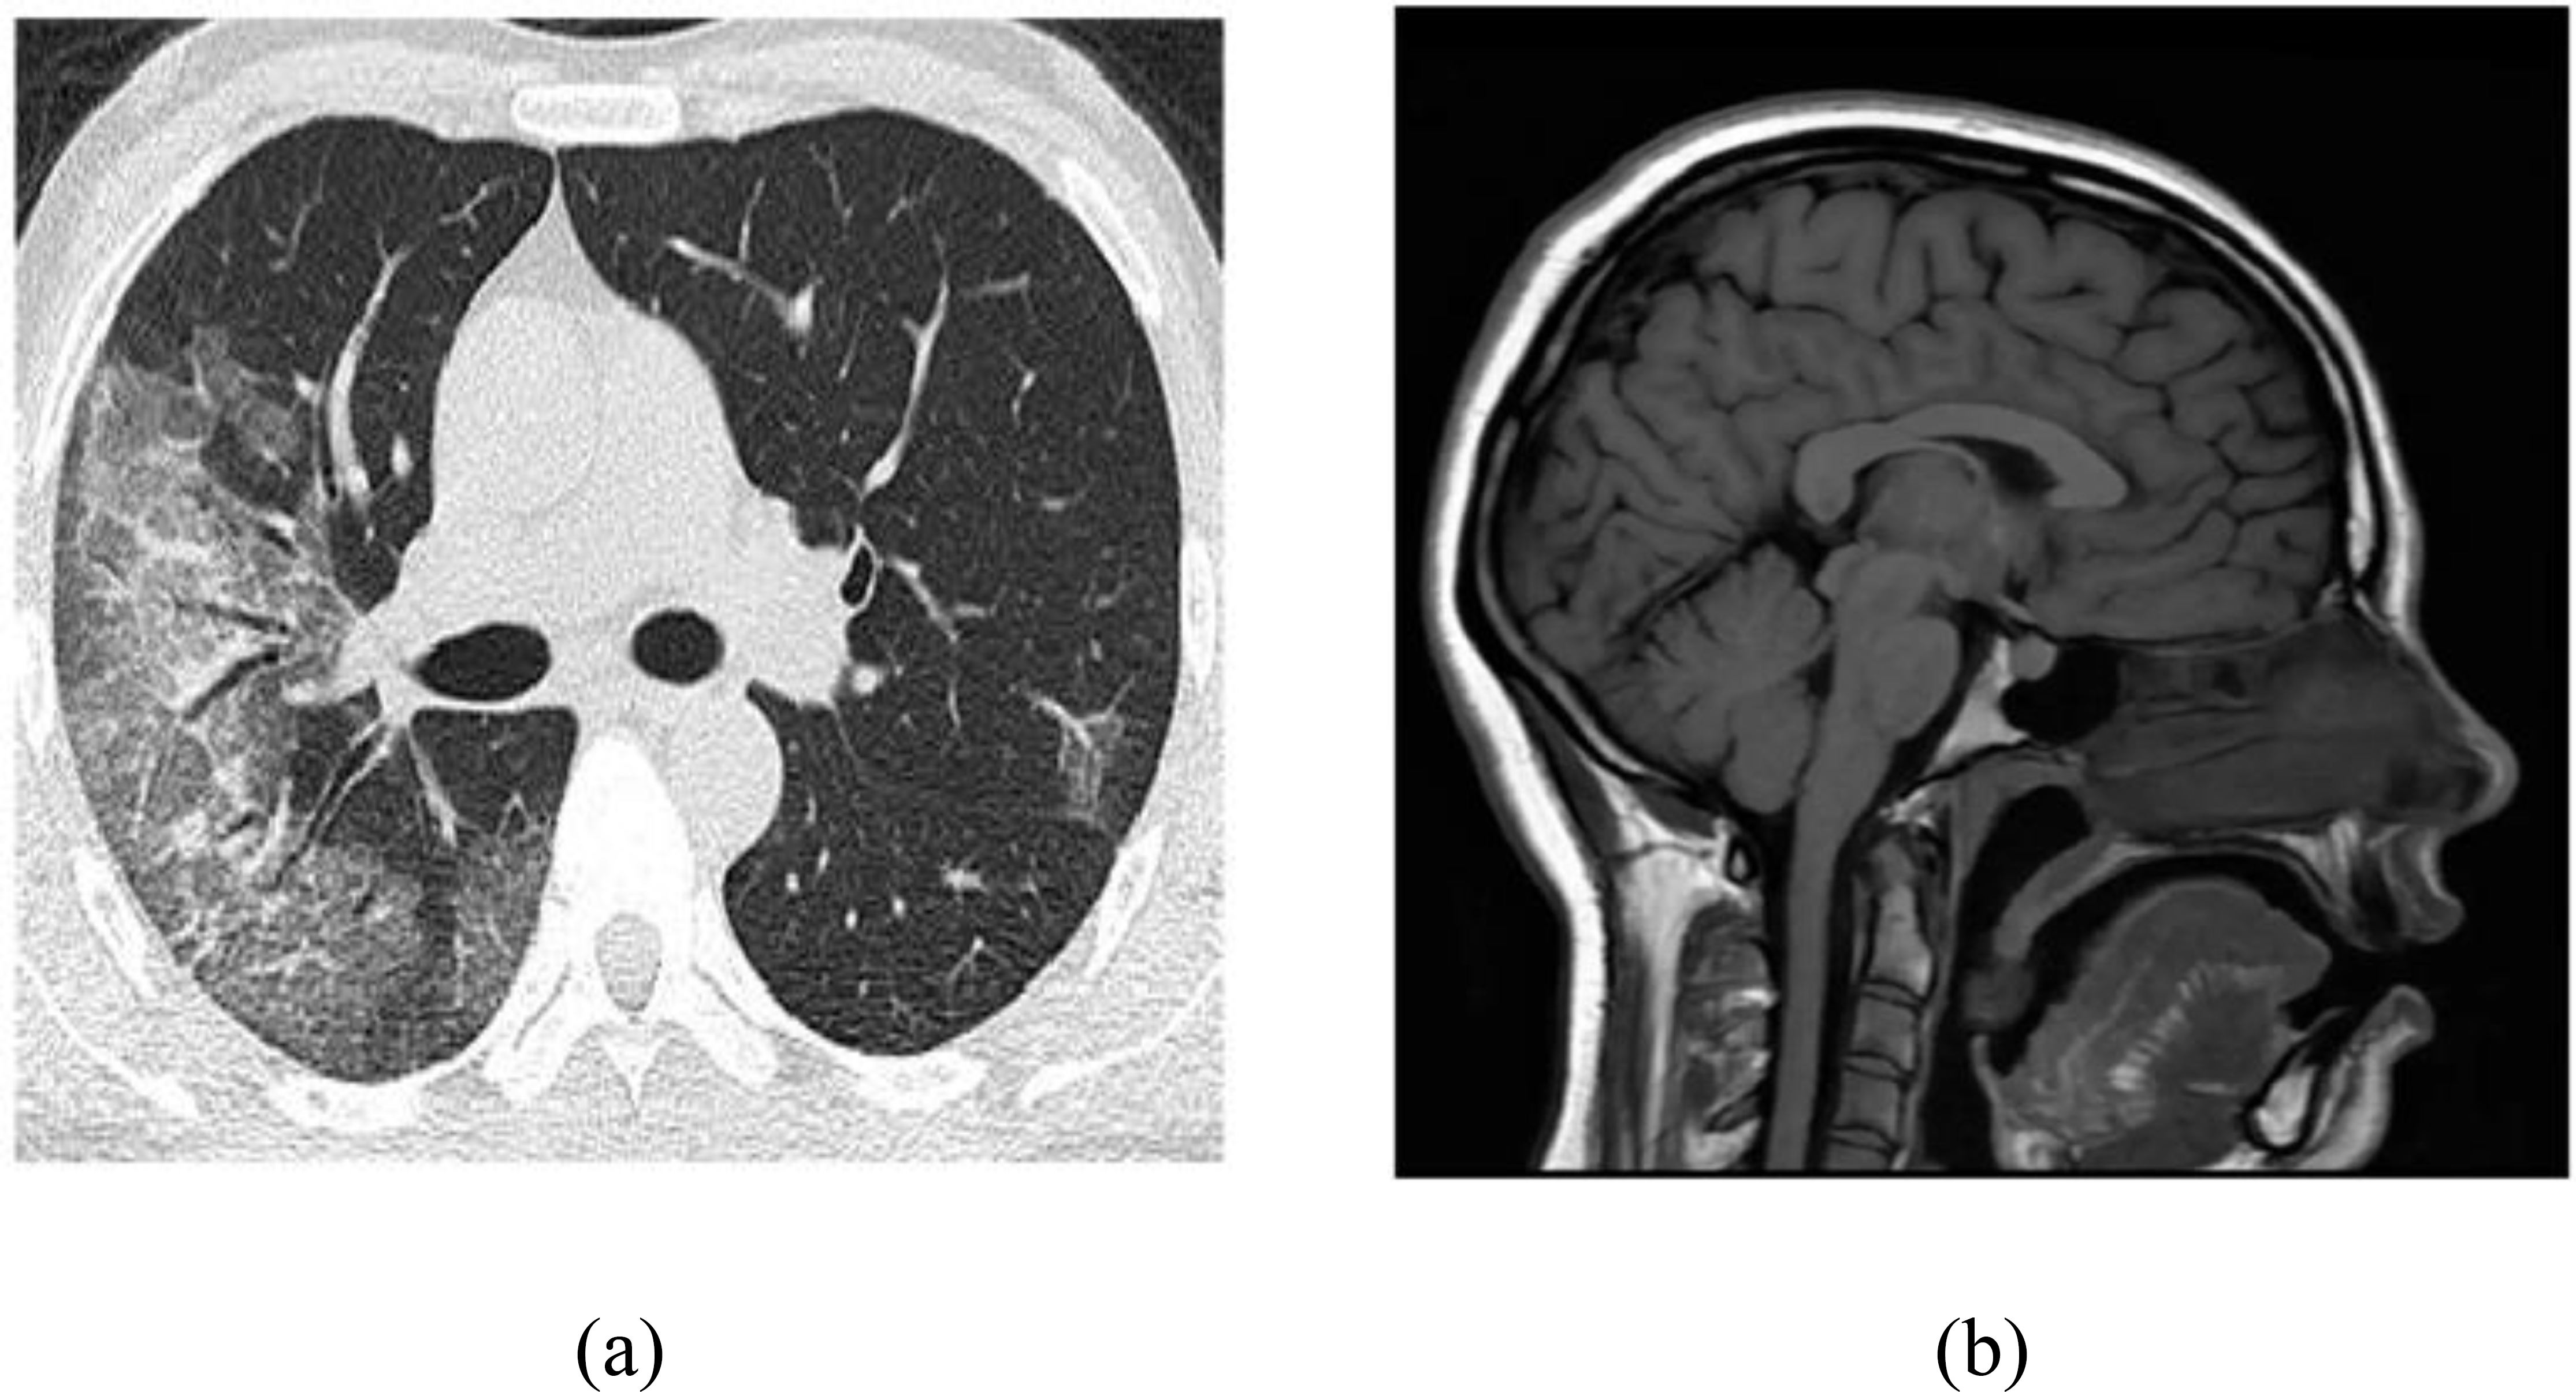

Two types of images are used: HRCT and MRI (Fig. 1a, b). The dataset is open source and publicly available [26].

(a) Dataset1 (HRCT Image), (b) Dataset2 (MR Image).

Figure 1a shows chest HRCT in which lung tissue is scanned in narrow slices of 1-2 mm, whereas in Figure 1b, a T1-weighted MRI sequence is shown.